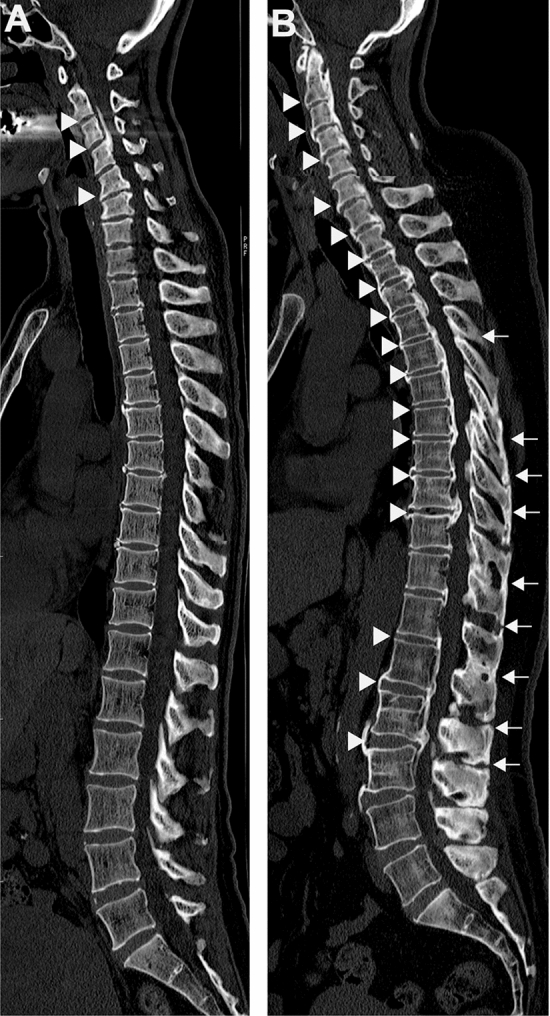

Figure 1.

Sagittal reconstruction CT images of the entire spine in patients with OPLL. (A) A representative case from the localized-OPLL group. A 57-year-old woman without NAFLD (the L/S ratio: 1.41) had OPLL (arrow heads) in the cervical spine. (B) A representative case from the diffuse-OPLL group. A 49-year-old woman with NAFLD (the L/S ratio: 0.94) had multilevel OPLL and OALL of the whole spine (arrow heads) and multilevel OLF and OSIL in the thoracolumbar spine (arrows). NAFLD, non-alcoholic fatty liver disease; OPLL, ossification of the posterior longitudinal ligament; OALL, ossification of the anterior longitudinal ligament; OLF, ossification of the ligamentum flavum; OSIL, ossification of the supra/interspinous ligaments.